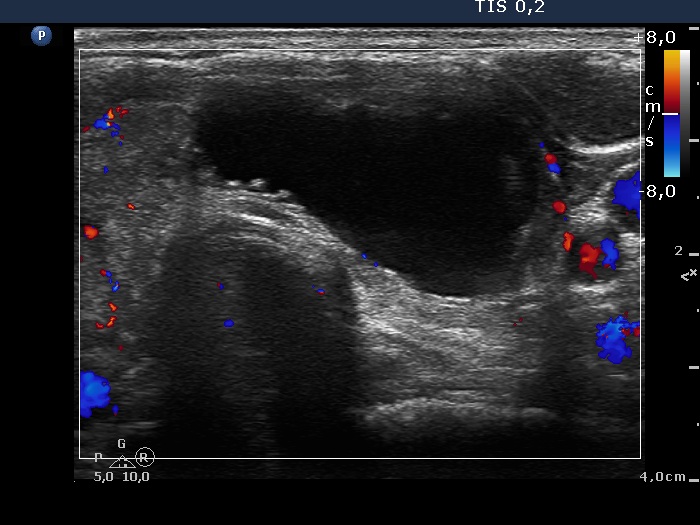

First examination (1st row of images)

Clinical presentation: a 29-year-old woman was referred for evaluation of a thyroid nodule discovered by the patient herself. She was treated for hypothyroidism for 3 years.

Palpation: both thyroids were firm. An elastic nodule was palpable in the left thyroid.

Functional state: hypothyroidism on daily 50 microgram levo-tiroxine with TSH-level 11.7 mIU/L.

Ultrasonography: the thyroid was hypoechogenic and presented fibrosis. There was an echonormal lesion in the central part of the right thyroid while a mixed, spongiform cyst occupied great proportion of the left lobe. The nodule in the left lobe presented signs of perinodular blood flow.

Cytology of the nodule in the left lobe resulted in cystic degeneration without any signs of malignancy.